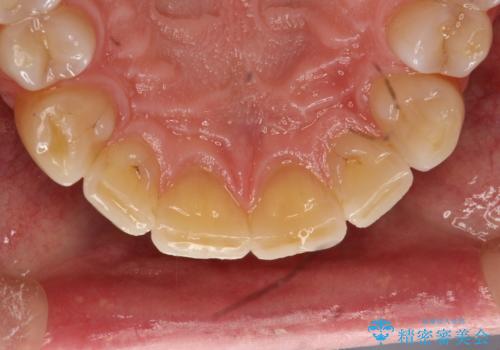

- 歯と歯の間の歯石が気になるとのことで来院されました。PMTC30分コースを行いました。プラークコントロールも悪かったため、歯ブラシ指導も行いました。